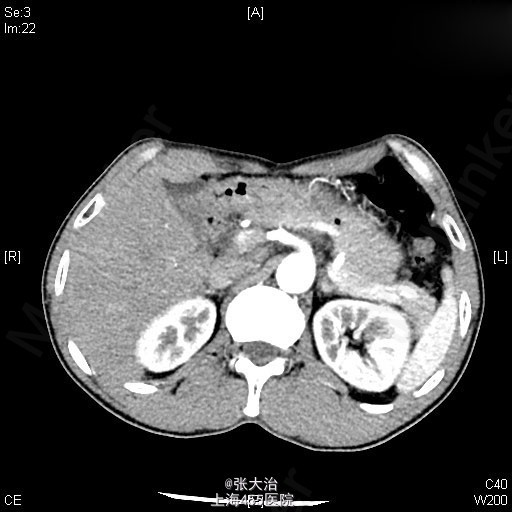

查体:神志清晰,精神尚可,呼吸平稳,营养中等,表情自如,发育正常,自主体位,应答流畅,查体合作。全身皮肤无黄染,无肝掌、蜘蛛痣。全身浅表淋巴结无肿大,无明显贫血貌,左锁骨上淋巴结(-);腹部平坦,未见肠型或胃蠕动波,未见腹壁静脉曲张;全腹软,无压痛、反跳痛、肌紧张。肝脾肋下未及,包块未及;移动性浊音(-),肠鸣音正常,每分钟约3次,不伴高调音、气过水声。 2014-4-10某人民医院就B超(92301):肝囊肿,左肝内胆管扩张;MRI(1697647):肝门区病变可能伴左肝内胆管扩张。 2014-4-22某人民医院MRCP(68941):肝门处占位伴肝内胆管扩张,考虑胆管细胞癌可能大,肝多发囊肿。 肝动脉CTA、门脉CTV、肝静脉CTV、下腔静脉CTVCT【2014-05-05 我院】 :肝门区MT,肝左、右动脉及门脉主干、左支受侵;肝及双肾小囊肿。 上腹部平扫+增强+DWI+MRCPMRI【2014-05-06 我院】 :肝左叶MT(胆管细胞型机会大)伴肝左叶胆管扩张,门脉受侵;肝、双肾小囊肿。 肝脾及门脉;胆(含胆总管);肾+输尿管;胰超声【2014-05-05 我院】 :超声造影:肝门部偏左侧实质占位--考虑肝门部胆管MT,侵犯门脉左支可能;肝左叶胆管扩张;右肾囊肿 肝脏超声造影超声【2014-05-05 我院】 :超声造影:肝门部偏左侧实质占位--考虑肝门部胆管MT,侵犯门脉左支可能;肝左叶胆管扩张;右肾囊肿 肝脏术后(检查胸水、腹水、手术区、膈下)超声【2014-05-20 我院】 :右侧胸腔少量积液;腹水